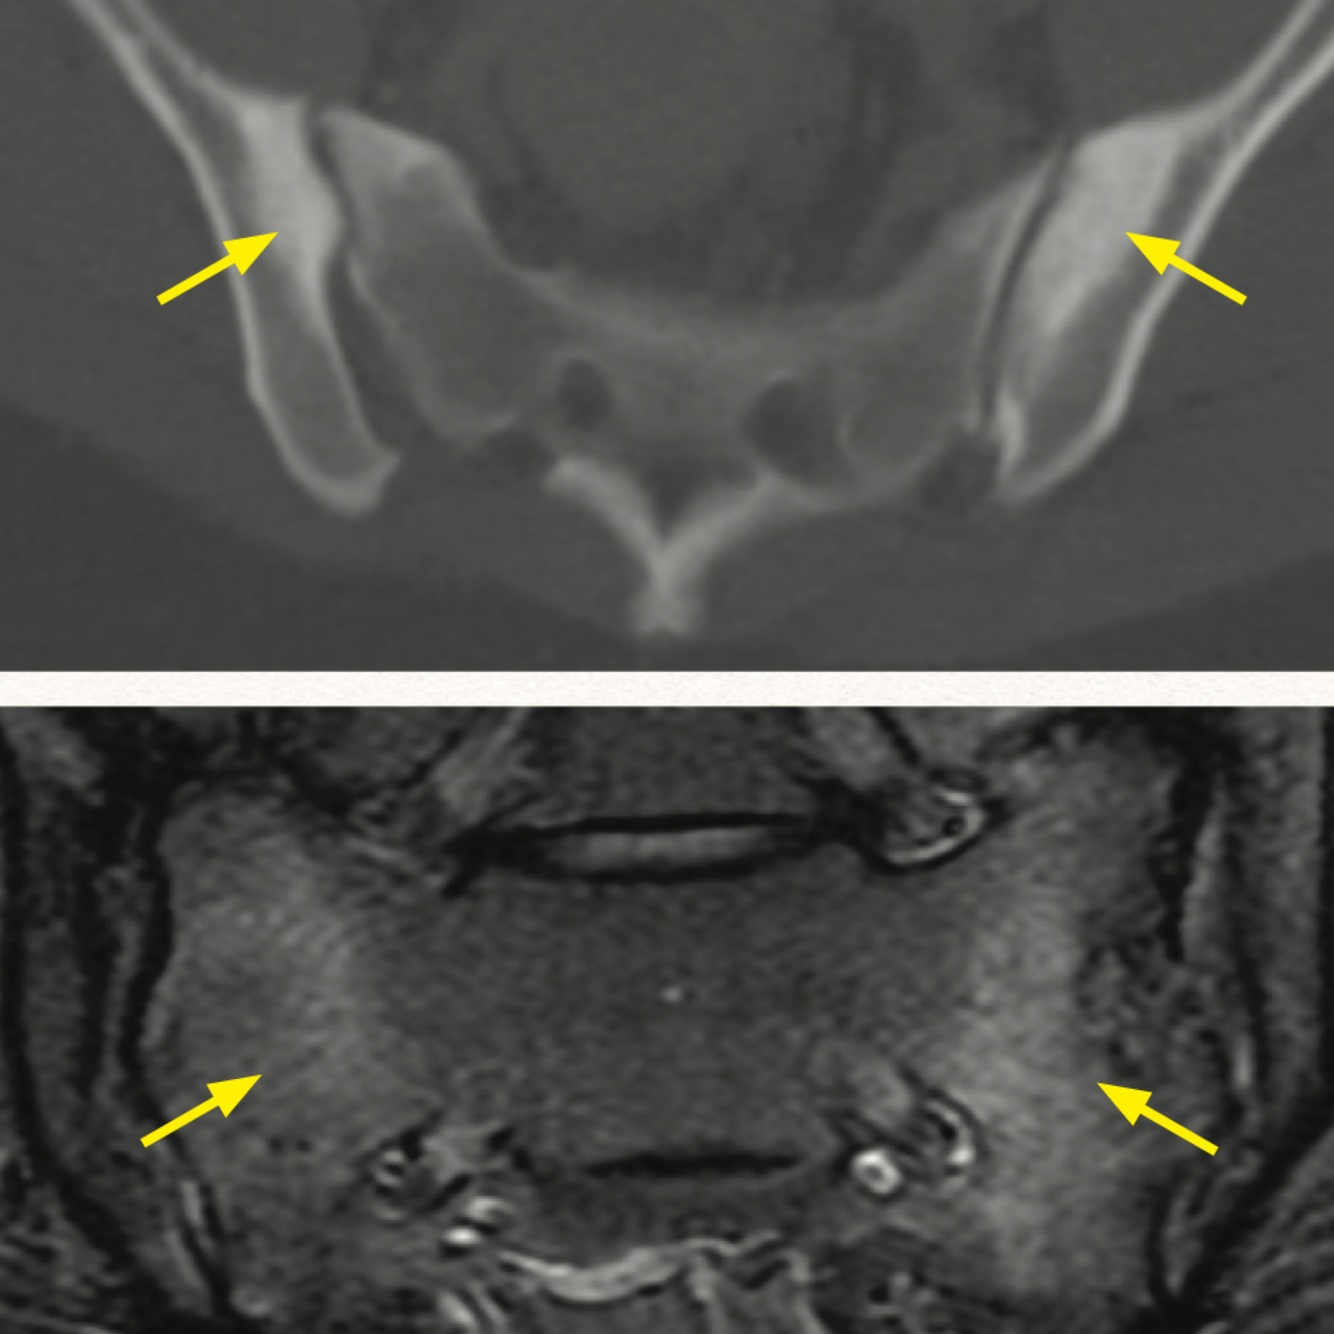

What is this finding and what is it associated with?

A

Symmetric sacroiliitis; IBD and ankylosing spondylitis

How well did you know this?